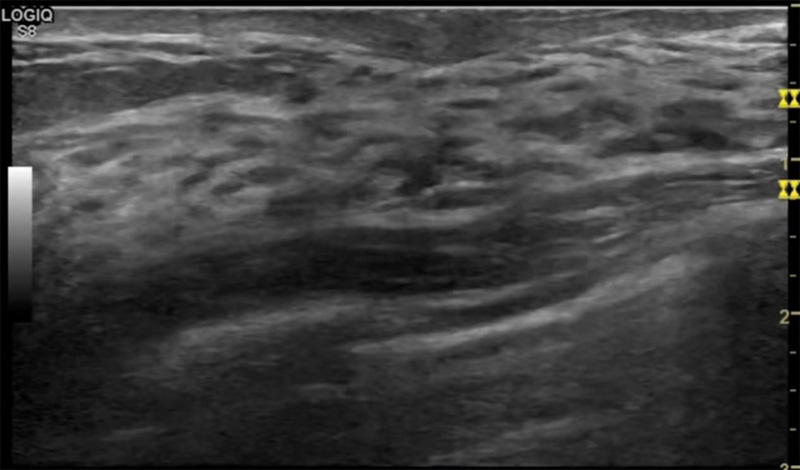

乳房胀痛,触摸疼痛,手摸起来感觉有肿块。这个是什么问题呢?医生诊断一般是乳腺增生。那么在乳腺成人抖音视频APPP在线观看检查后,报告单却显示双乳未见明显占位性病变。乳腺增生是很多女性,特别是育龄期女性都有的经历、到底乳腺增生症状有哪些?会给91抖音视频在线观看带来怎样的影响呢?乳腺增生不是肿瘤跟炎症。乳腺组织增生及退行性变跟内分泌功能紊乱有关系。正常的生理改变。还有乳腺病,良性乳腺结构不良等名称。

乳腺增生有什么症状,病因?比较典型的就是乳房疼痛,特别是经前症状比较重,经后就有所缓解。有时候还能碰到乳房硬块。根据经期的变化而变化硬度大小都有变。乳腺在内分泌激素,伴随月经周期有增生问题。内分泌激素代谢失衡,雌激素水平增高,出现乳腺组织增生过度,增生组织不退的情况下,就会有乳腺增生症状。这个不会增加乳腺癌的风险。所以不用紧张的。不过乳腺癌的病人都会有乳腺增生。所以乳腺增长有没症状,都需要进行常规的体检。